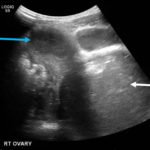

Due to pain out of proportion to her exam, an ultrasound of her pelvis was obtained and showed a blood-filled distended uterus, or hematometrocolpos (white arrow), with a 4.9 cm right ovarian cyst (blue arrow). A pelvic magnetic resonance imaging (MRI) then revealed an obstructed right hemi-vagina, normal left uterus and vagina and ipsilateral renal agenesis (red arrow) with normal left kidney (double arrow) consistent with obstructed hemivagina, ipsilateral renal agenesis (OHVIRA) syndrome. The patient underwent surgical repair with complete resolution of symptoms.